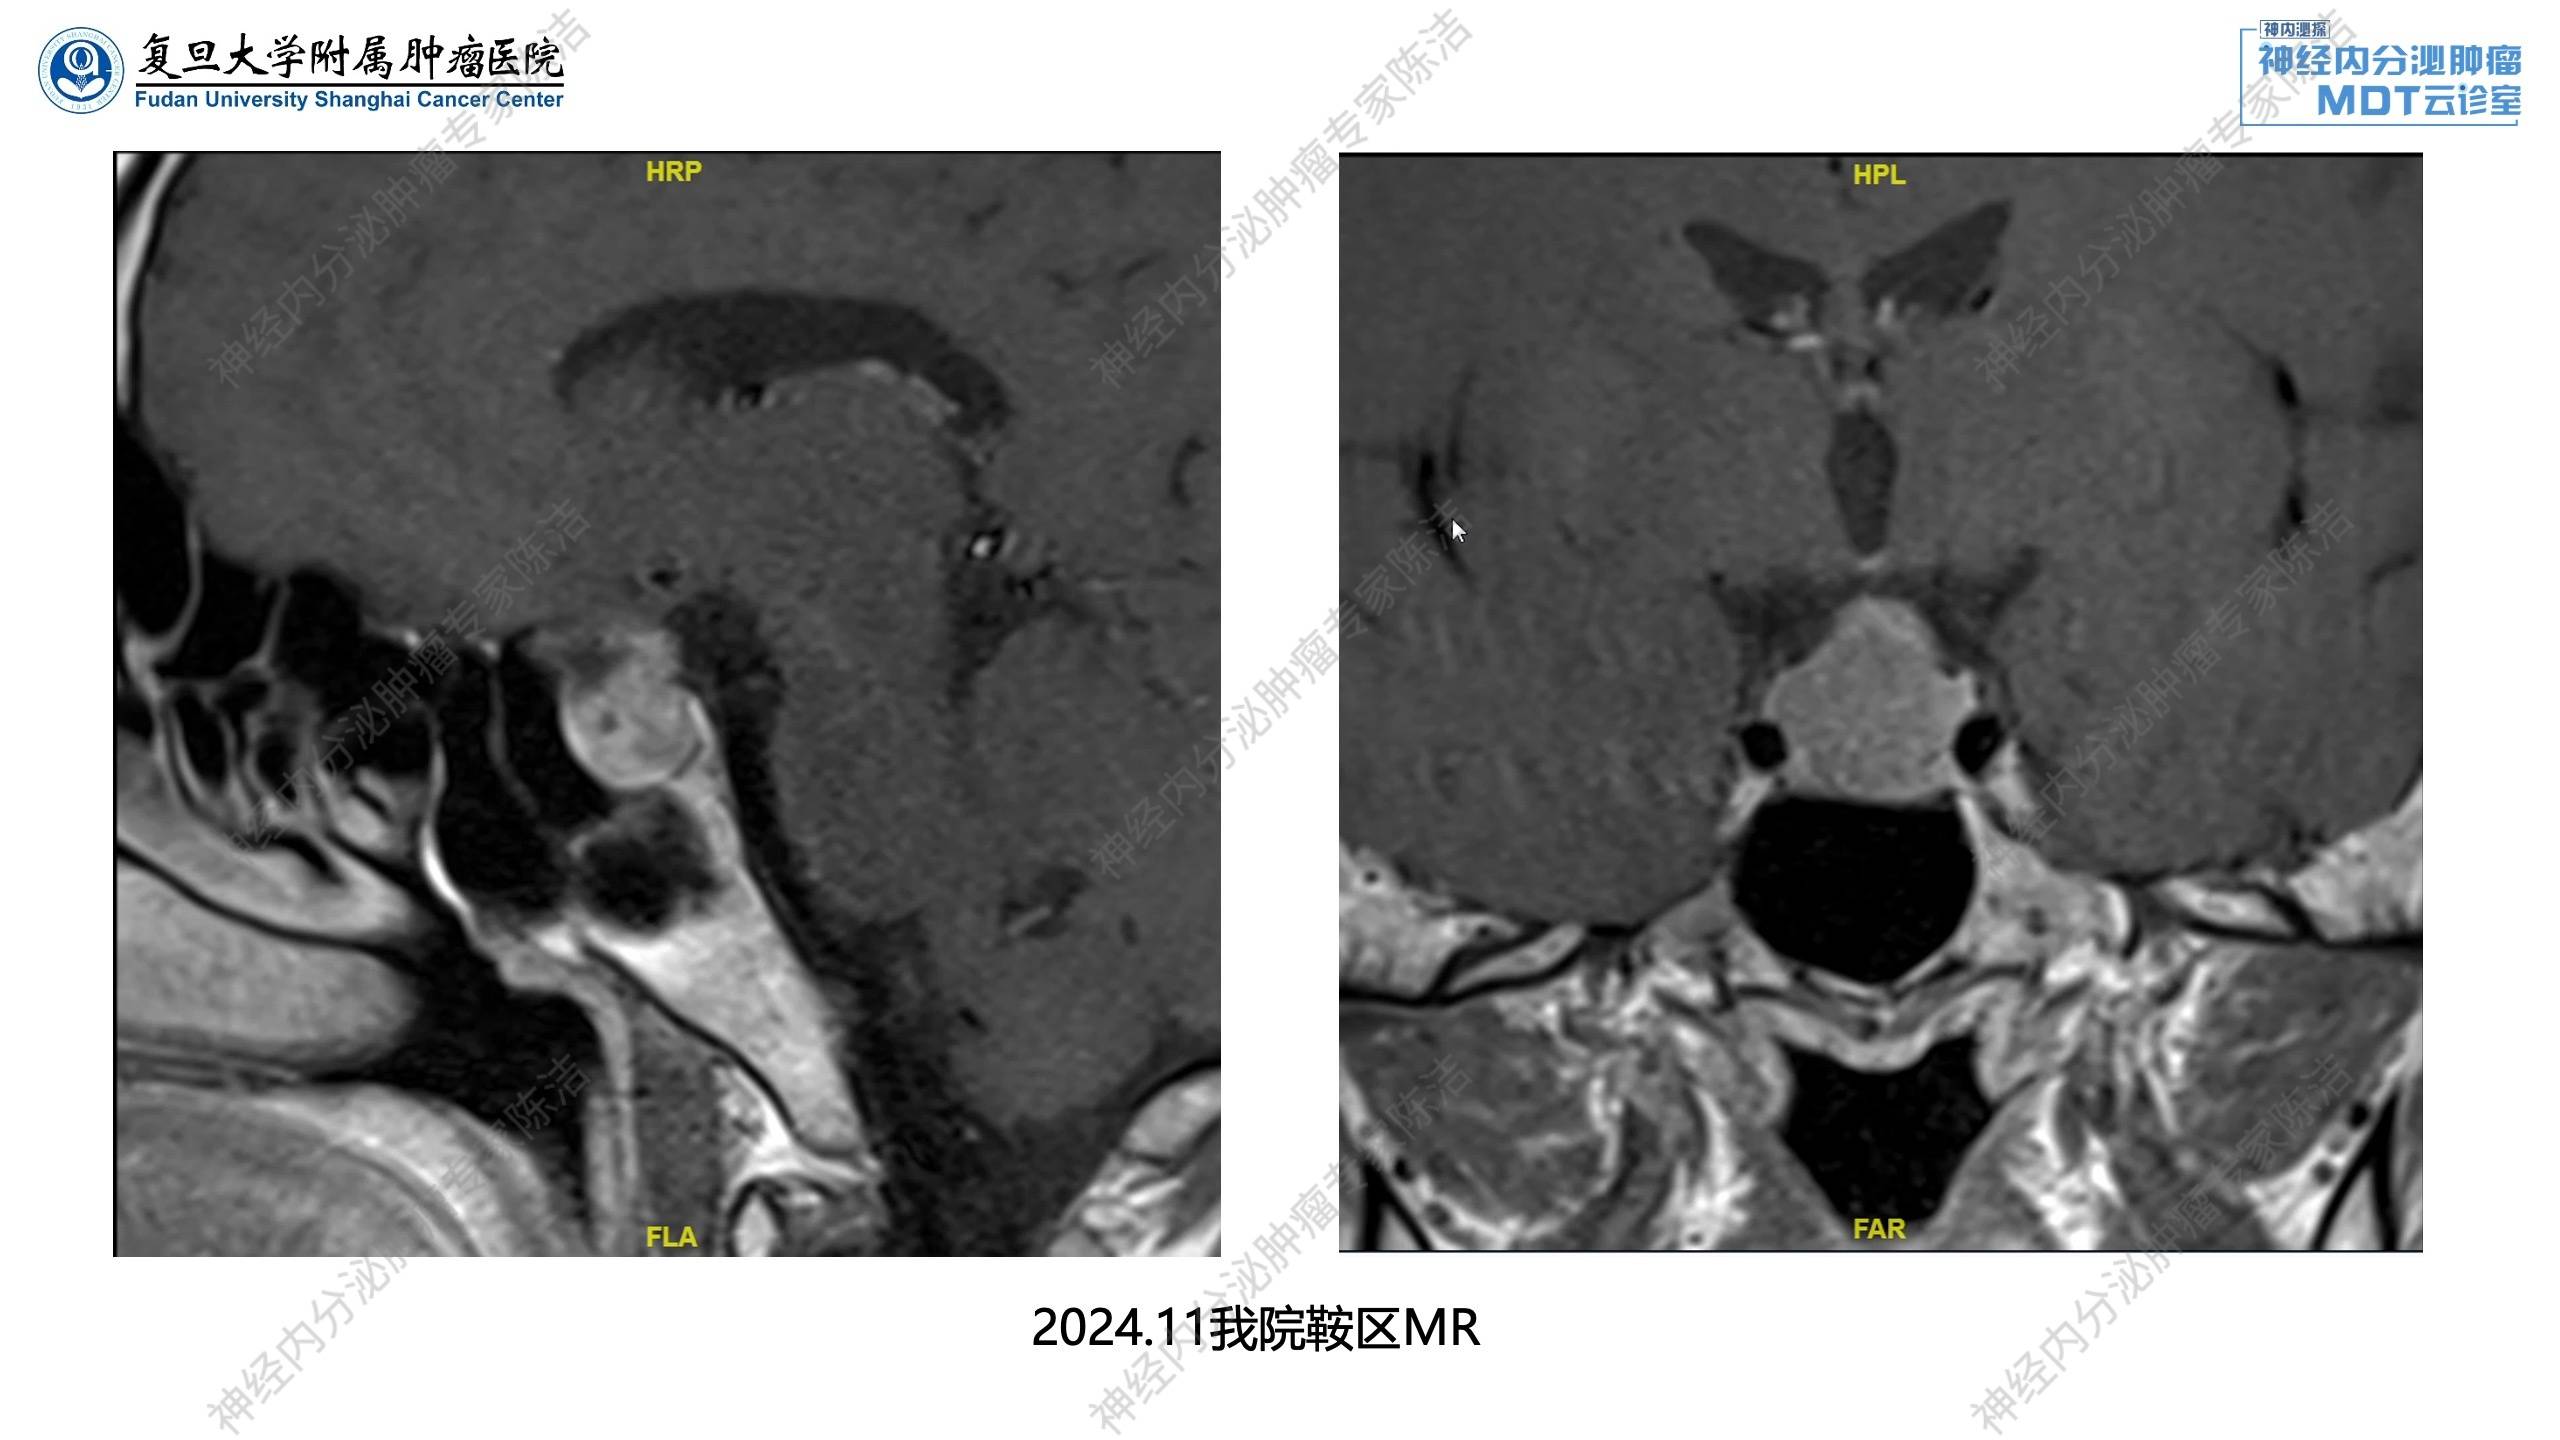

鞍区MRI示鞍区较大占位伴囊变,考虑垂体NET。

放射诊断科汤伟教授:术前增强CT跟核医学PET结果一致,经观察发现存在两个较大的病灶,同时胰头部位亦有若干较小病灶,可明确为多灶性pNET。垂体MRI提示鞍区有个比较大的占位,两侧海绵窦受压,考虑垂体神经内分泌肿瘤改变。